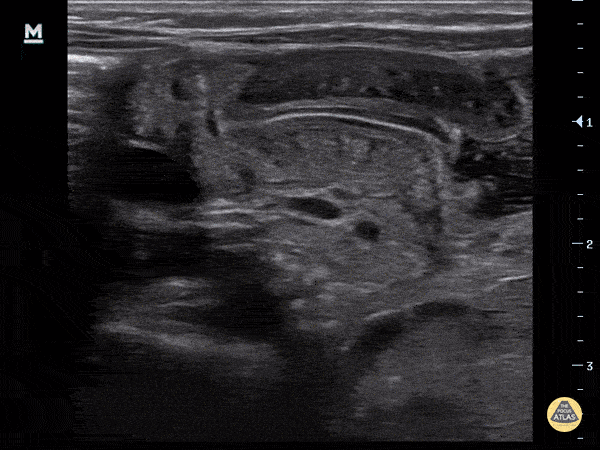

Peds-Gastrointestinal - Pyloric Stenosis (Longitudinal)

4-week-old, vomiting intermittently for 2 weeks, seen PCP 3 days ago, reassured. Revisit today and PCP concerned for pyloric stenosis, so referred to ED. Exam in ED reassuring for well-appearing neonate. In ED, POCUS completed revealing hypertrophic pyloric stenosis. Pylorus muscle hypertrophied and thickened in both transverse and logitudinal view. Transverse view demonstrates the classic target sign seen in pyloric stenosis. Dr. Sathya Subramaniam, Pediatric EM Fellow - Kings County/SUNY Downstate